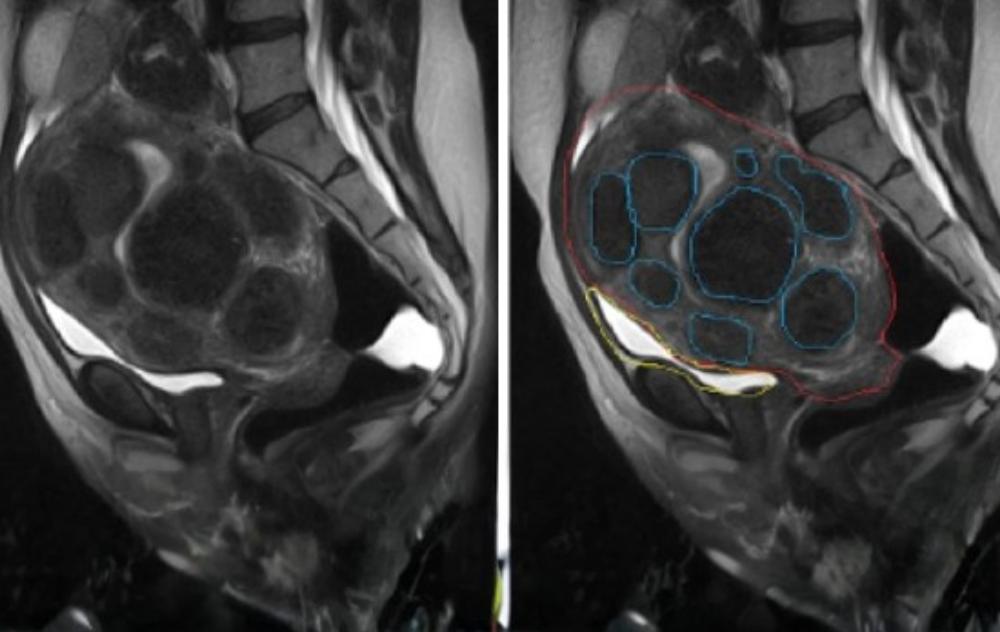

While the fibroid in this example is small, many patients deal with multiple, larger growths that significantly alter the shape of the uterus, as seen in the following scans:

What do uterine fibroids look like?

Internally, uterine fibroids are dense, white, circular masses of muscular tissue. They can range in size from a tiny “poppy seed” to a large “grapefruit” or even a “melon.” On an MRI scan, they typically appear as dark, well-defined round objects within or on the walls of the uterus.